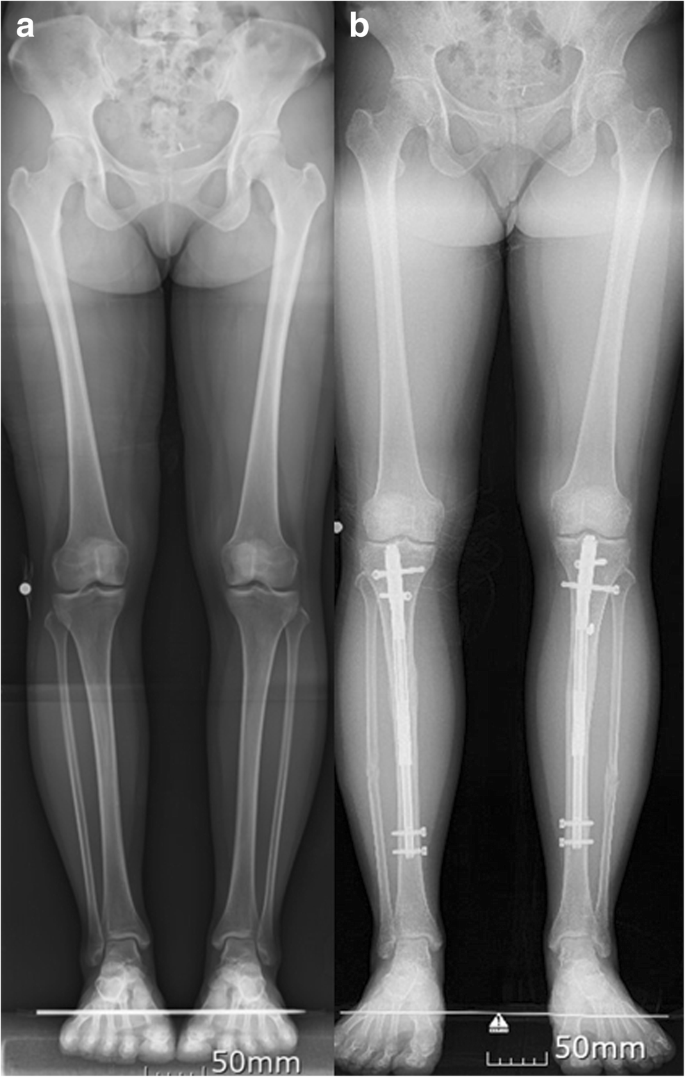

Cosmetic Limb Lengthening India - I undergone a limb lengthening surgery myself, i searched many doctors that tim.